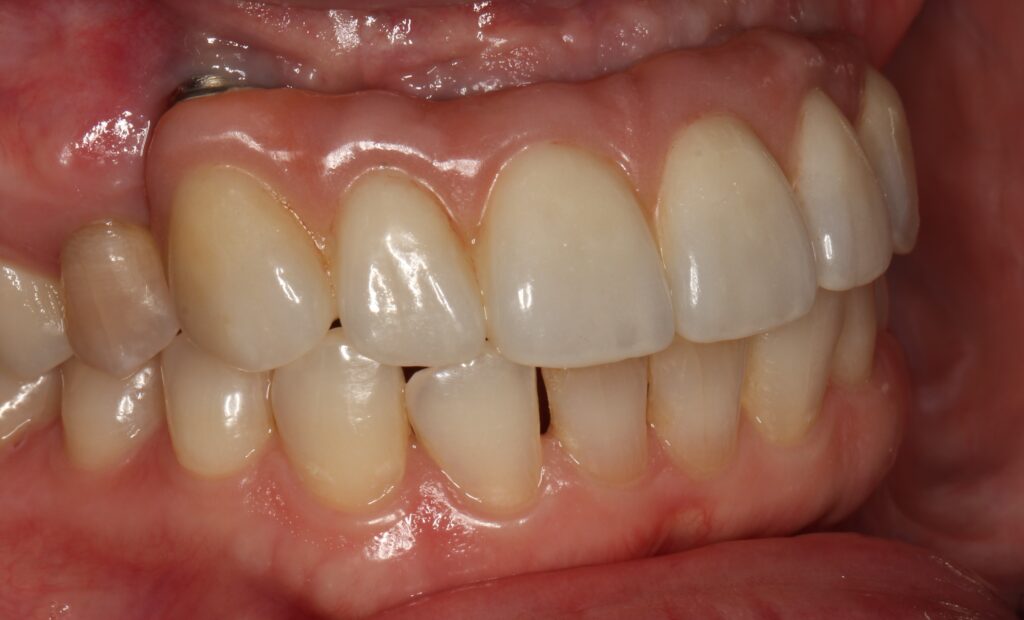

A selection of partial arch fixed implant bridge patients